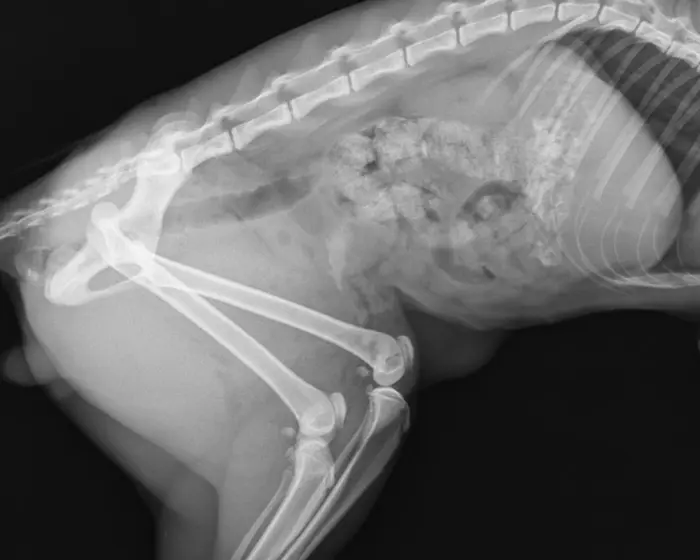

Røntgen af dit kæledyr

Løkken Dyreklinik er i besiddelse af digitalt røntgenudstyr. Vi udfører de fleste former for røntgendiagnostik, her kan nævnes undersøgelse for hofteledsdysplasi, albueledsdysplasi, osteochondrose, slidgigt mm. Den digitale teknik har optimeret vore røntgenbilleder og dermed også de diagnostiske muligheder.